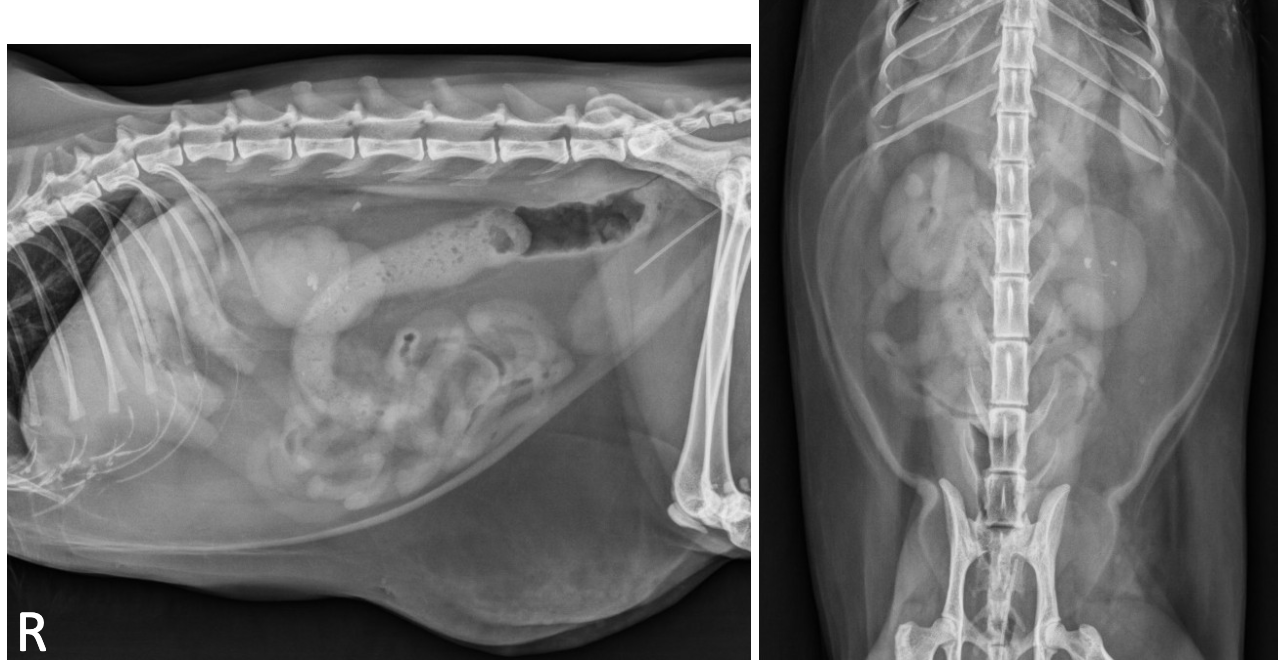

bilateral renomegaly with irregular margins with many cysts in the cortex that are anechoic with distal acoustic enhancement

PCRD